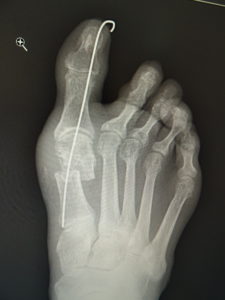

手術前 手術後4年

最近では、原則として固定ワイヤーは経皮的の一本のみとし、ワイヤーの先端は皮膚の外に出ているので、抜く時(術後3週間目)の患者さんの負担はほぼありません。こうすることによるデメリットはなく、むしろ術後成績は良くなっています。

手術前 手術後

真田理事長による手術の様子。外反母趾|症例 (左から 手術前、手術後、ワイヤ抜去後)